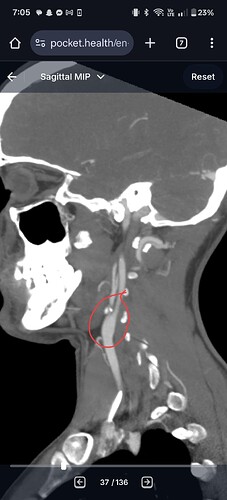

Hi everyone. So grateful to find this place and all of you. You have no idea how much you have helped me already. I had an elongated styloid process on the left side only (3.9cm), and I was diagnosed with ES and underwent the transcervical styloidectomy on 06/12/25, so I’m just about two months post surgery.

However, the glossopharyngeal nerve in the back of my throat is very angry. We double checked my imaging to make sure it wasn’t being compressed, and it isn’t. It’s just angry. One of my main symptoms all along was difficulty speaking because of the pain and tension in my throat, and this nerve is definitely still causing that for me, even though the additional pain in the left side of my neck is WAY better. Is this normal? Does the glossopharyngeal nerve just take a lot longer to heal or calm down? I know we probably upset it more with the surgery, so maybe it’s just still recovering and I need to be patient?